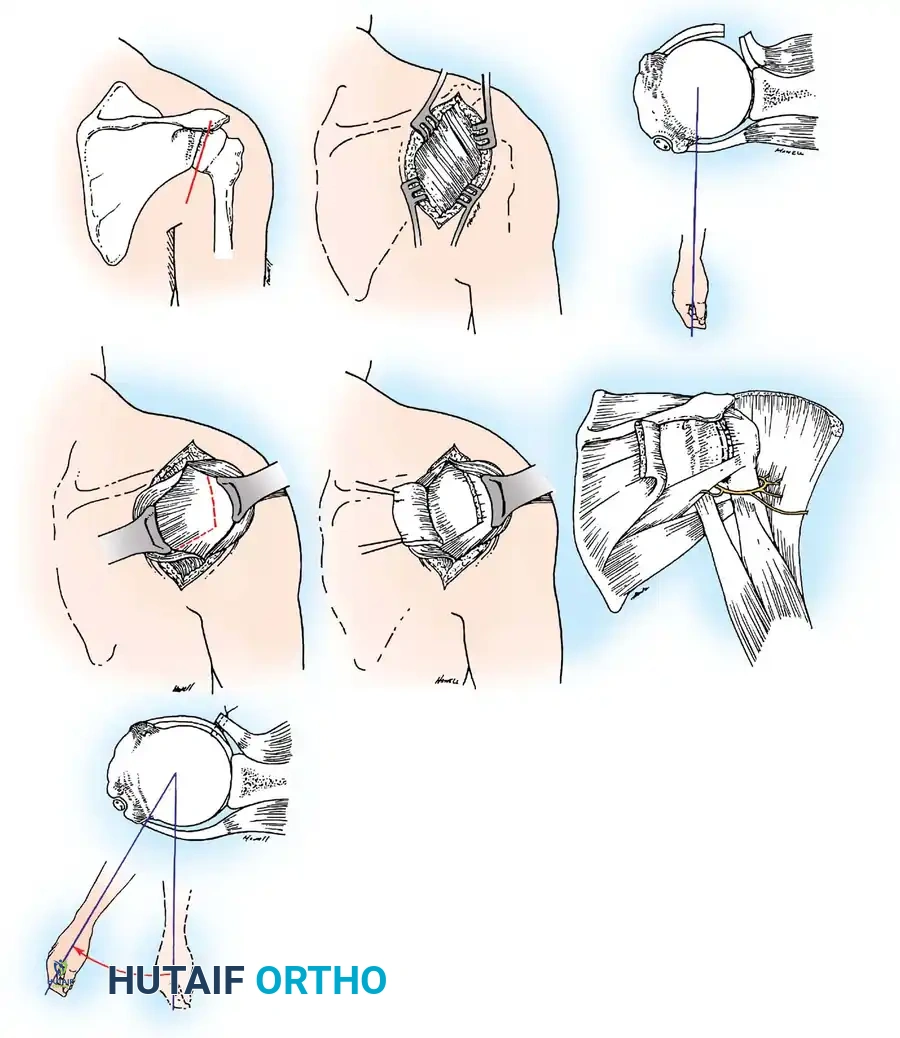

Surgical Management: Open Anterior Stabilization

While arthroscopic stabilization has become the gold standard for isolated soft-tissue Bankart lesions, open anterior stabilization remains a critical technique for revision cases, patients with poor capsular tissue, or those requiring concomitant bony augmentation (e.g., Latarjet procedure).

- Presence of glenoid bone loss (>15-20%) necessitating a coracoid transfer (Latarjet) or bone block.

Surgical Approach: The Deltopectoral Interval

- Incision: A standard 5 to 7 cm incision is made starting from the tip of the coracoid process, extending distally and laterally toward the deltoid insertion.

- Superficial Dissection: The cephalic vein is identified within the deltopectoral groove. It is generally retracted laterally with the deltoid to preserve its venous drainage, though medial retraction with the pectoralis major is acceptable if lateral tributaries are sparse.

- Deep Dissection: The clavipectoral fascia is incised lateral to the conjoint tendon (short head of biceps and coracobrachialis). The conjoint tendon is retracted medially. Care must be taken to avoid aggressive medial retraction, which can cause a neurapraxia to the musculocutaneous nerve (typically entering the coracobrachialis 3-5 cm distal to the coracoid).

Subscapularis Management

Exposure of the anterior capsule requires navigating the subscapularis muscle. Historically, a vertical tenotomy was performed; however, modern techniques favor a subscapularis split or a peel to preserve the integrity of the muscle belly and its tendinous insertion.

- The Split: A horizontal split is made in the subscapularis at the junction of its middle and inferior thirds, extending from the lesser tuberosity medially.

- Separation: The subscapularis is carefully elevated off the underlying anterior joint capsule. This plane can be scarred in revision cases, requiring meticulous sharp dissection to avoid inadvertent capsulotomy.

Glenoid Preparation and Labral Repair

The essential step in restoring stability is the anatomical reduction of the capsulolabral complex to a bleeding bone bed on the anterior glenoid rim.

- Debridement: The anterior glenoid neck is decorticated using a motorized burr, rasp, or osteotome to create a bleeding cancellous bed. This promotes robust biological healing of the repaired labrum.

- Mobilization: The scarred, medially displaced labrum (ALPSA lesion) must be fully mobilized using a periosteal elevator until the subscapularis muscle belly is visible anteriorly. The tissue must float freely to be shifted superiorly and laterally.

- Anchor Placement: Suture anchors (typically 3 to 4) are placed along the articular margin of the anteroinferior glenoid (from the 5:30 to 3:00 positions for a right shoulder). Anchors must be inserted at a 45-degree angle to the articular surface to maximize pullout strength and avoid joint penetration.